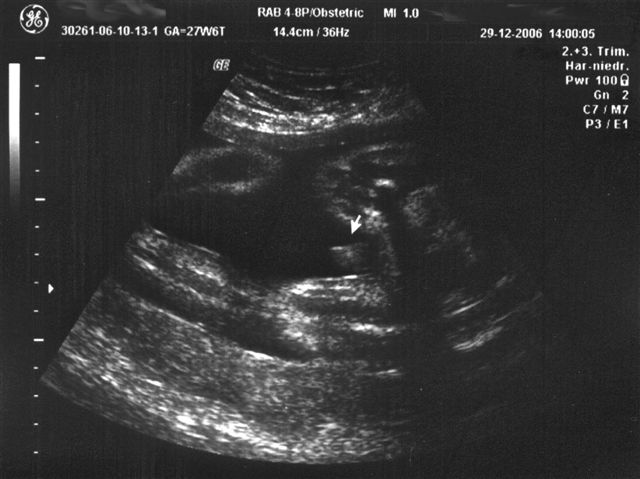

27+6 SSW

Waaaaaahnsinn, was sich in den letzten 7 Wochen getan hat. Richtig Speck hat der Kobold angesetzt. Verschlafen war er heute auch. Das CTG war dem Doc zu "ruhig" - also noch mal mit "Bauchschüttel-Wecken"...."Na also, geht doch" meinte der Doc und war zufrieden.

Beim anschließenden Ultraschall ist u.a. obiges Bild entstanden . Papa und der große Bruder waren mit und beide waren gleichermaßen fasziniert.

Kurzum: Alles dran, alles in Ordnung und absolut zeitgerecht entwickelt. 1.100 g wiegt er schon und ist etwa 25 cm lang, wobei die Länge nur geschätzt ist und nach oben und unten variieren kann.